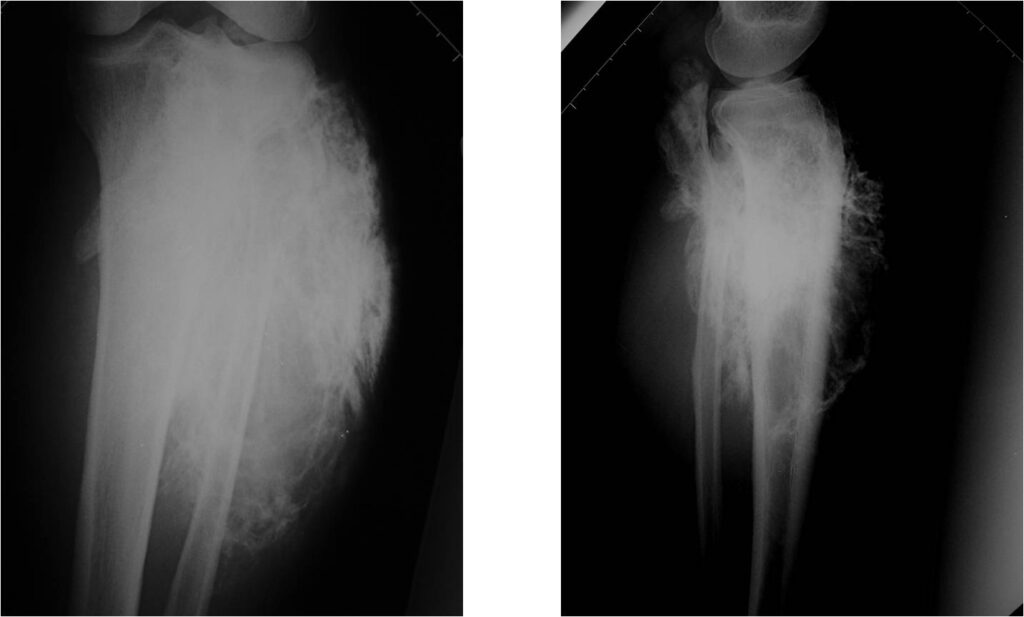

Radiographic Presentation: Conventional Osteosarcoma

There are 3 radiographic presentations for osteosarcomas, depending upon the amount of osteoid/ossification and calcium deposition:

- Mixed sclerotic and lytic, permeative lesion most common radiographic presentation

- Purely osteoblastic, permeative lesion: dense sclerosis and osteoid production

- Purely lytic, permeative lesion: little osteoid production and/or minimal calcium deposition in osteoid

Conventional osteosarcomas are permeative lesions on plain radiographs (borders of the lesion cannot be clearly delineated)

- Wide zone of transition from lytic/sclerotic areas of tumor to normal bone

- Makes borders of lesion hard to define

- Most (90%) arise from the metaphysis of the bone

- Rarely (10%) arise from the diaphysis

- Most conventional osteosarcomas (90-95%) extend through the bone into the soft tissues and form a soft tissue mass outside of the bone